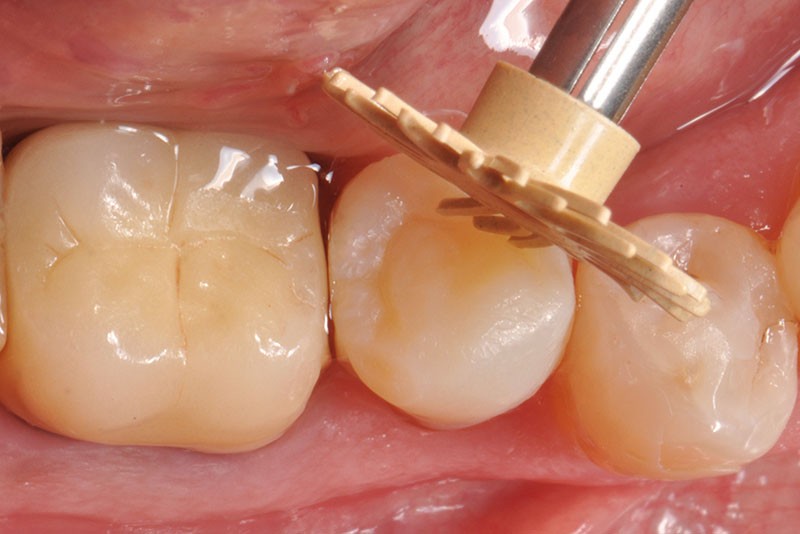

27, 28, 29. La couronne transitoire est pré-polie avec la roue spirale 3M™ Sof-lex™ beige puis polie avec la roue spirale diamantée 3M™ Sof-lex™ rose.